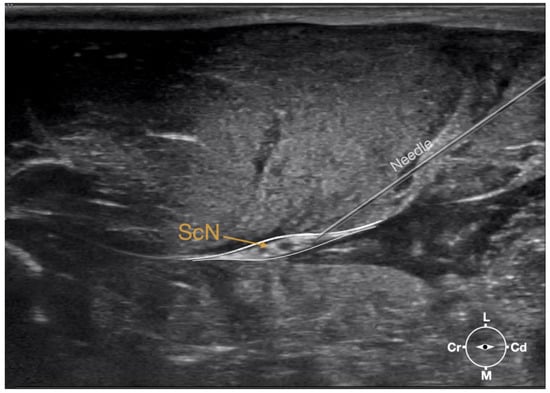

2.3.1. Sciatic Nerve Injection

First, the cadaver was positioned in lateral recumbency. Then, the area of interest was clipped. A 18-4 MHz linear transducer (L 18-4, Konica Minolta, Ramsey, NJ, USA) attached to an ultrasound machine (HS1, Konica Minolta, USA) was used and ultrasound gel (Softa-Man, ViscoRub, B. Braun, Maria Enzersdorf, Austria) was applied to facilitate acoustic coupling. The transducer was placed in transverse position, at the level of the proximal third of the femur but caudal to the bone with a window of interest set at a depth of 3 cm to optimize the image. Then, the transducer was slightly rotated clock or anticlockwise to obtain a transverse image of the sciatic nerve (Figure 1). A 50 mm 22-gauge insulated needle (Sonoplex Stim Cannula, Pajunk Medical Produkte GmbH, Geisingen, Germany) prefilled with a solution of L-NMB was inserted using an in-plane approach. The needle was inserted at the caudal end of the transducer and advanced in-plane under sonographic guidance through the biceps femoris muscle in a cranio-medial direction towards the sciatic nerve (Figure 2). The needle was advanced until its tip punctured the muscular fascia enveloping the sciatic nerve (Figure 3). A test volume of 0.05 mL of L-NMB was injected to confirm adequate distribution inside the interfascial space that contained the sciatic nerve. The remaining volume of 0.15 mL/kg was then injected perineurally around the sciatic nerve.

Figure 3. Ultrasonographic image demonstrating the approach of the needle towards the sciatic nerve. Depth at 3 cm and focus on the level of the nerve. ScN, sciatic nerve; Cr, cranial; Cd, caudal; L, lateral; M, medial.